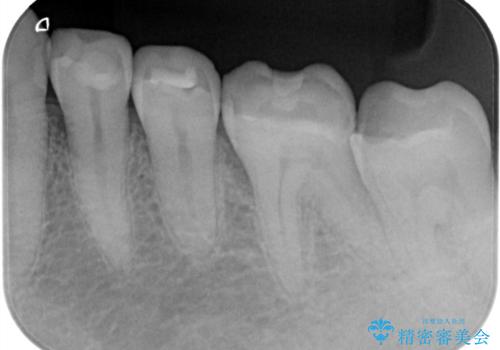

よく見ると歯冠部に咬合面から近心側にのびるヒビ(クラックライン)が入っているのが見えます。

「噛むと歯が鈍く痛む」を主訴に来院されました。

各種検査を行い、咬合面にヒビ(クラック)を認めました。

元々咬合面にレジンインレーが入っており、近心歯質が薄くなっていたことや、食いしばるクセを持っていることも、ヒビが入った要因の一つと考えられます。